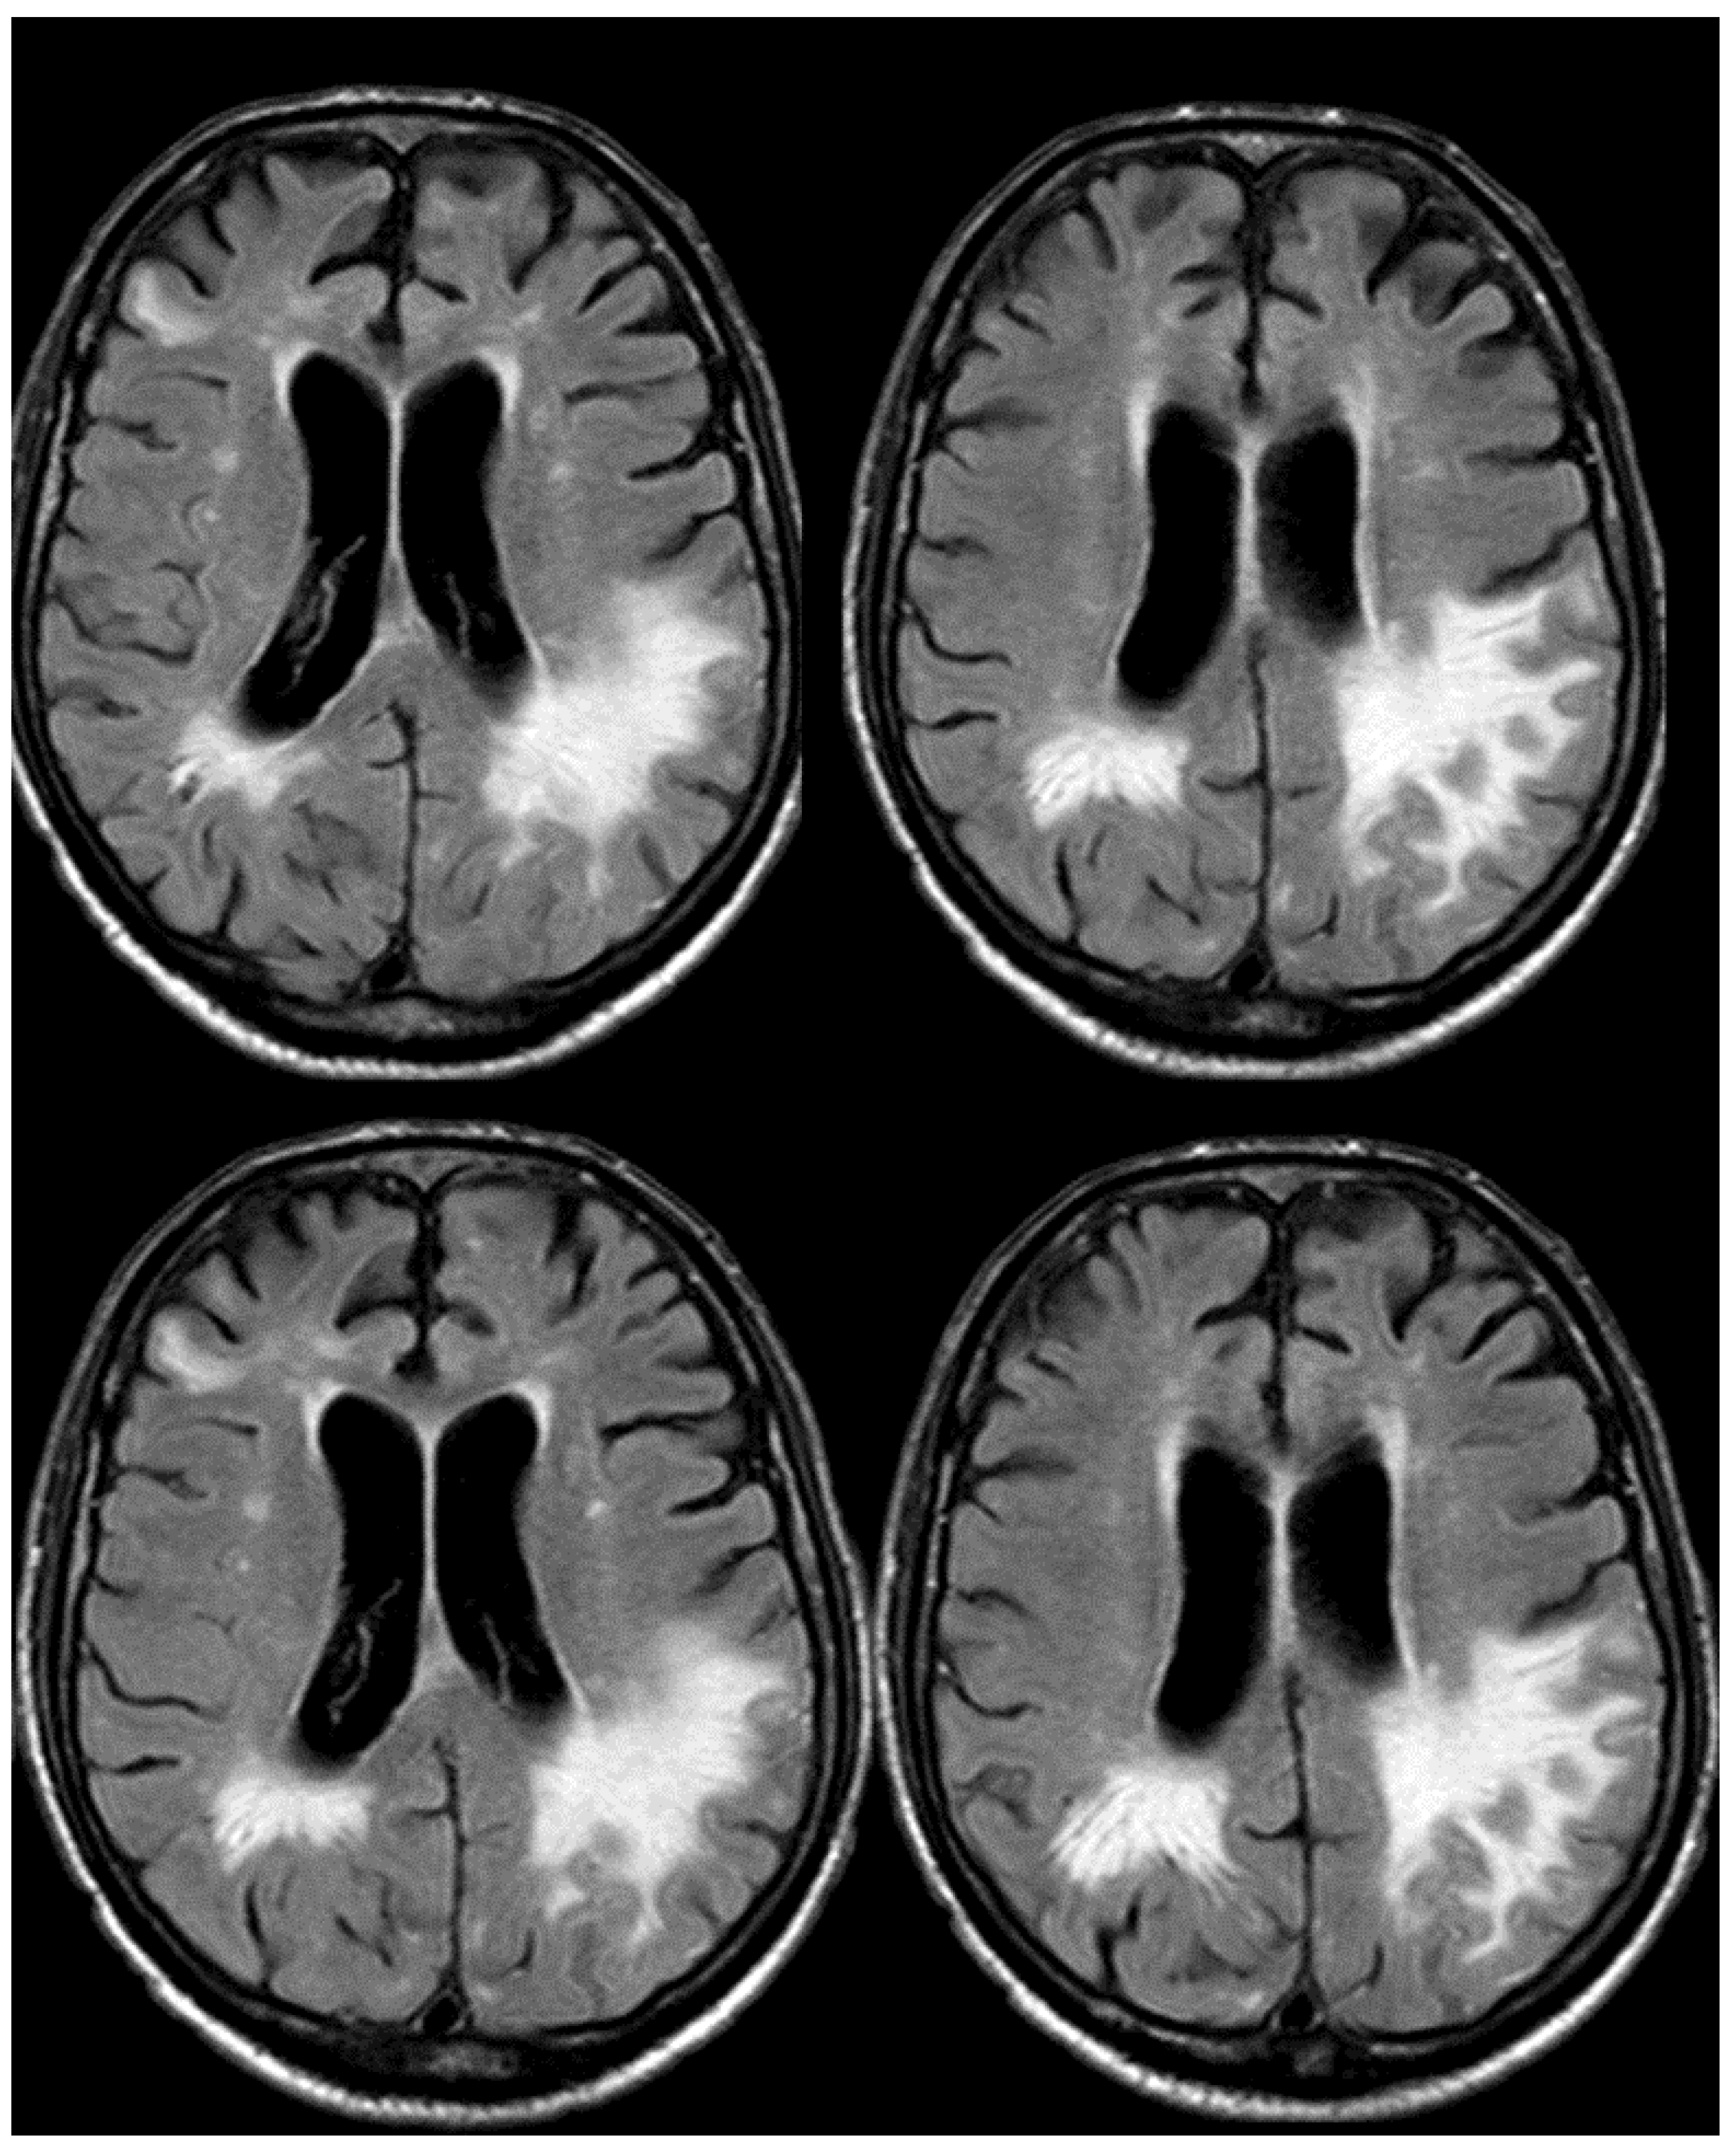

3. May 2014: CAA-Related Inflammation

5. February 2017: First Recurrent CAA-Related Inflammation

7. April 2018: Second Recurrent CAA-Related Inflammation

8. April 2018: Third Recurrent CAA-Related Inflammation